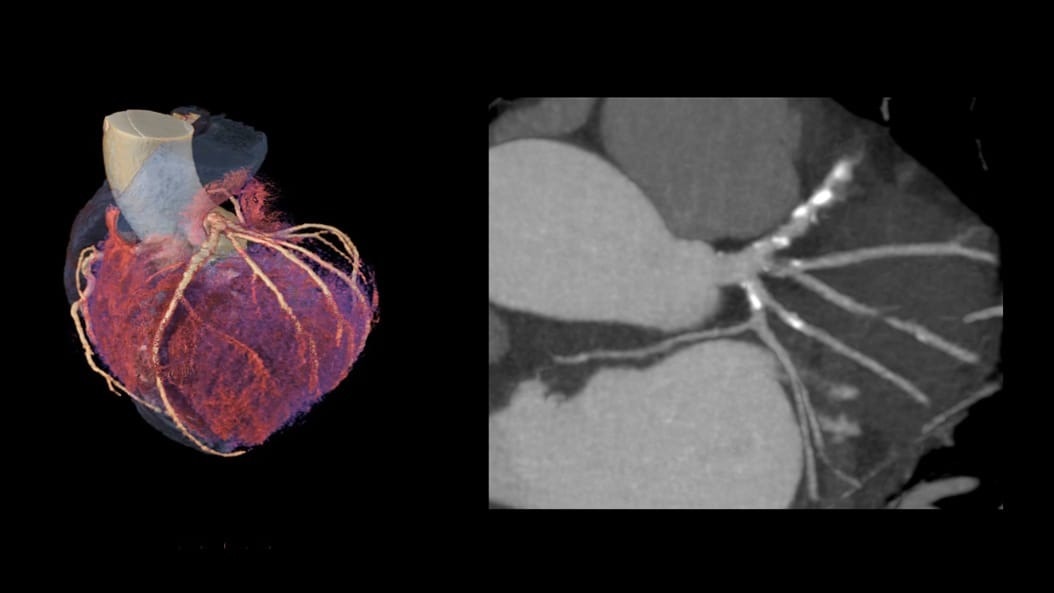

CardiQ Suite

An integrated suite of CT Cardiac post-processing tools, built for automation and workflow efficiency.

Consistency

>90% concordance with CACS‑DRS classification grouping⁵

Identification

>95% correct identification of the presence of coronary artery calcifications⁵

Labeling

>90% accurately labeled coronary artery territories⁵